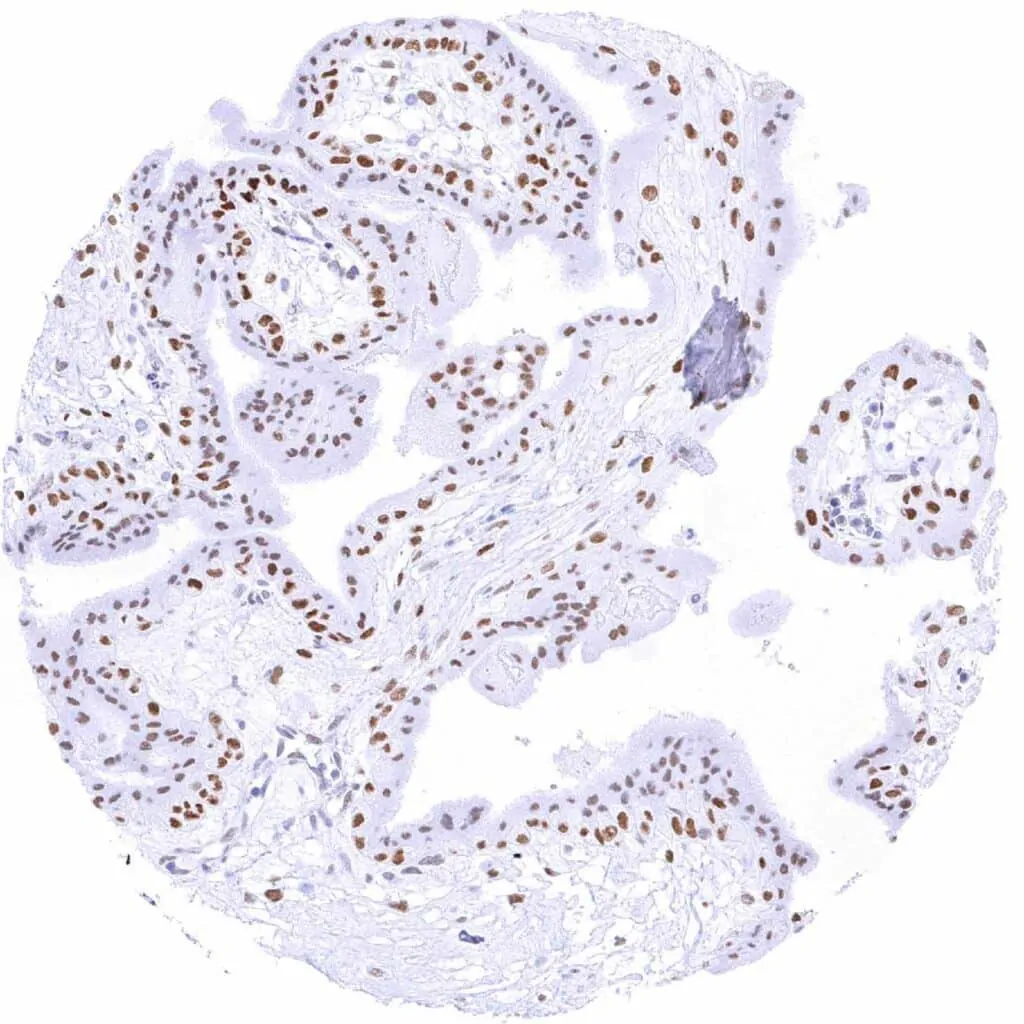

Prostate – Weak to moderate TLE1 staining in acinar cells. Staining is weak or absent in basal cells